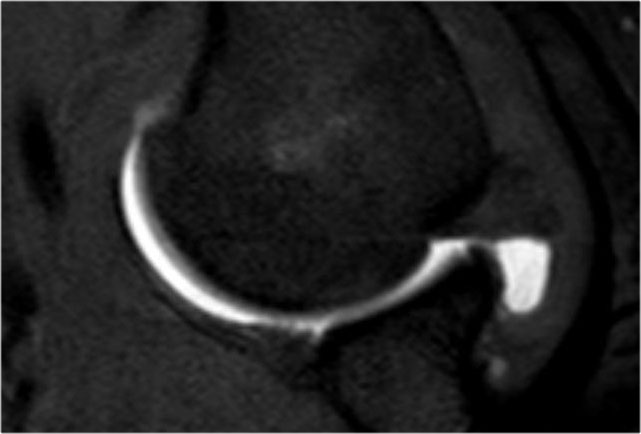

Tổn thương Perthes

Tổn thương Perthes là avulsion sụn viền-dây chằng tương tự Bankart, nhưng với màng xương bị bóc tách về phía trong mà vẫn còn nguyên vẹn.

Trên hình ảnh khớp vai ở tư thế trung gian, sụn viền bị rách có thể được giữ ở vị trí giải phẫu bình thường bởi màng xương bả vai còn nguyên vẹn, từ đó ngăn thuốc tương phản từ thấm vào đường rách.

Điều này có nghĩa là MRI khớp cản từ ở tư thế trung gian có thể không phát hiện được đường rách sụn viền.

Tuy nhiên, ở tư thế ABER, dây chằng ổ chảo-cánh tay dưới bó trước bị căng tạo lực kéo lên sụn viền trước-dưới, giúp tăng khả năng phát hiện đường rách.

Mũi tên chỉ vào màng xương còn nguyên vẹn.

Các hình ảnh ở tư thế ABER cho thấy sụn viền trước bị bong tách.

Hình bên phải được xoay 90° ngược chiều kim đồng hồ.

Đôi khi điều này giúp hiểu rõ hơn về giải phẫu.